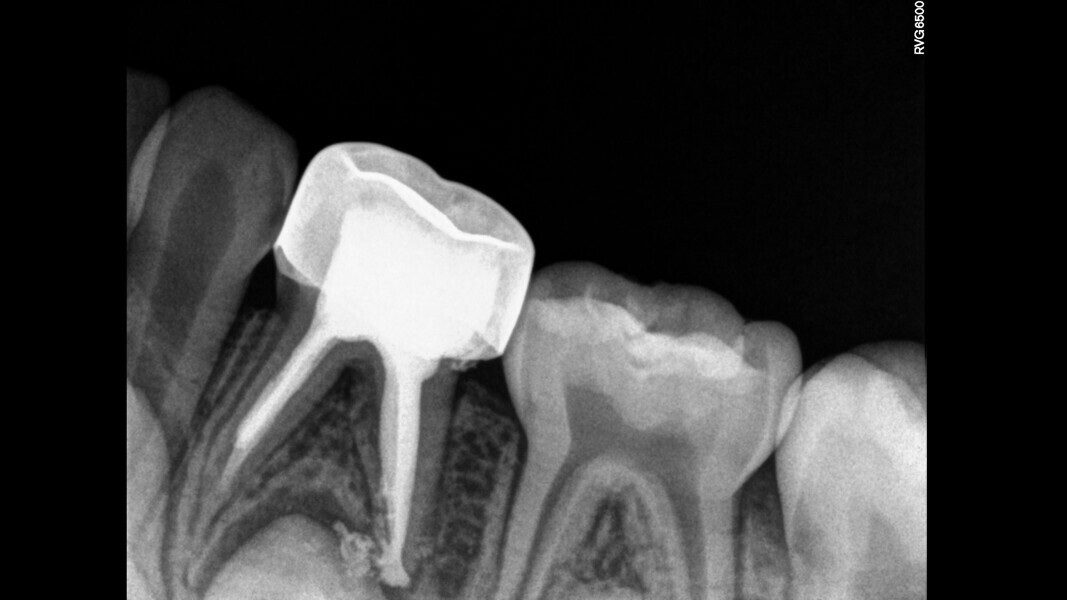

Case 1 (Figs. 1–4)

This female patient was 4 years and 7 months old and presented with pain that had lasted for several days affecting the mandibular right second primary molar. On clinical examination, a buccal gingival swelling and facial initial oedema were noted, and the tooth was found to have deep occlusal decay. Pulp necrosis and a symptomatic apical abscess were diagnosed. The patient was prescribed medication to control acute infection and rescheduled after the antibiotic treatment. At the second appointment, no pain was reported and the buccal abscess had partially receded. A decision was made to perform pulpectomy and restoration. Over-extrusion of the obturation material was observed. The 15-month re-evaluation confirmed no clinical or radiological signs of disease, and bone deposition was evident in the furcal area.